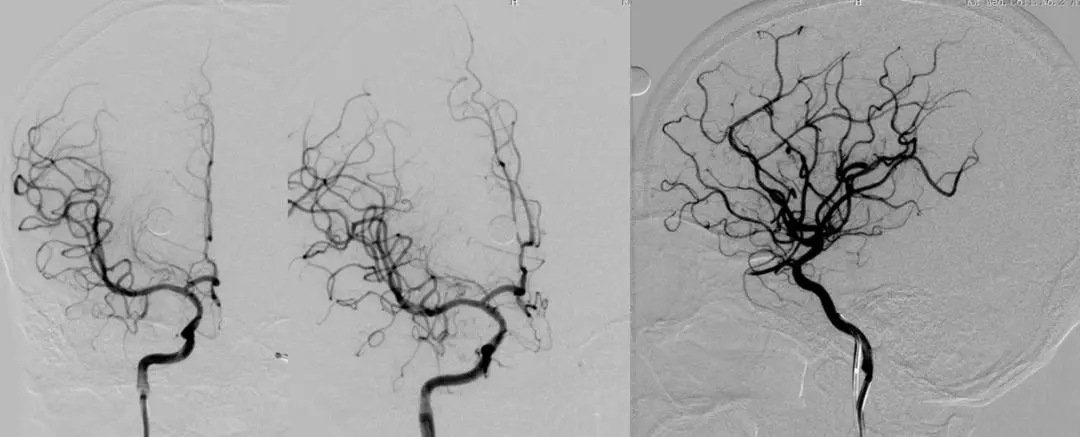

2周后行全脑血管造影术

DSA

右侧颈内动脉虹吸段闭塞

![]()

左侧颈内动脉造影见前交通开放,左侧大脑前动脉向右侧大脑前及大脑中动脉供血区部分代偿供血。

后循环代偿较差